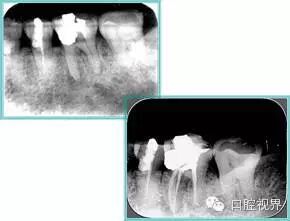

测量标准:以允许根管器械直线并直接进入根尖 1/3 且不接触冠方各壁为标准。

( 2 )髓腔其他改变:如髓室顶、继发性牙本质、修复性或增龄性牙本质。见左图。

右图中有继发性牙本质,切削后获得直线通路。